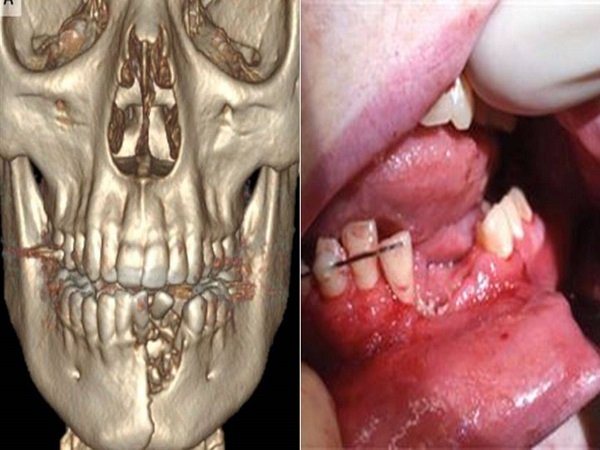

ಯುವಕನಿಗೆ ಚಿಕಿತ್ಸೆ ನೀಡುತ್ತಿರುವ ವೇಳೆ ಕೆಲವು ಹಲ್ಲುಗಳನ್ನು ತೆಗೆಯಲಾಯಿತು ಮತ್ತು ಹಾನಿಗೀಡಾಗಿರುವ ಅಂಗಾಂಶವನ್ನು ಕೂಡ. ಹಾನಿಯು ತೀವ್ರವಾಗಿದ್ದ ಕಾರಣದಿಂದಾಗಿ ಎಲುಬಿನ ಸ್ಥಿತಿರೀಕರಣಕ್ಕಾಗಿ ಕೆಲವು ಕೃತಕ ಅಂಗಾಂಶಗಳನ್ನು ಅಲ್ಲಿ ಅಳವಡಿಸಲಾಯಿತು.

ತನ್ನ ಮಗನ ಕೋಣೆಯಿಂದ ದೊಡ್ಡ ಮಟ್ಟದ ಸದ್ದು ಕೇಳಿಬಂತು ಮತ್ತು ಆತ ನೋವಿನಿಂದ ಕಿರುಚಾಡುತ್ತಿದ್ದ. ಆಕೆ ಆತನ ಕೋಣೆಗೆ ಹೋದ ವೇಳೆ ರಕ್ತವು ಒಸರುತ್ತಿತ್ತು ಮತ್ತು ಮುಖದಲ್ಲಿ ದೊಡ್ಡ ತೂತು ಕೂಡ ಆಗಿತ್ತು. ವೈದ್ಯರು ಈ ಘಟನೆಯನ್ನು ದ ನ್ಯೂ ಇಂಗ್ಲೆಂಡ್ ಜರ್ನಲ್ ಆಪ್ ಮೆಡಿಸಿನ್ ನಲ್ಲಿ ಪ್ರಕಟಿಸಲಾಗಿದೆ ಮತ್ತು ಇ ಸಿಗರೇಟ್ ಬಳಸುವ ಅಪಾಯವನ್ನು ಇಲ್ಲಿ ಹೇಳಲಾಗಿದೆ.